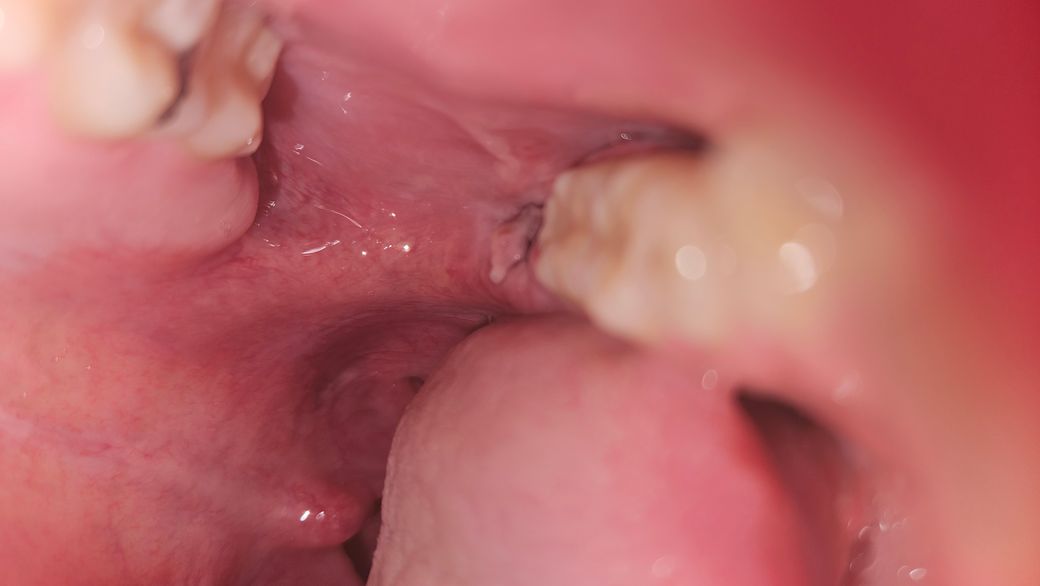

사랑니 양쪽 발치 5일차인데 원래 형태가 이런가요?

실밥은 제거한 상태인데 위로 꽤 솟아있는 느낌입니다. 원래 저런가요? 반대쪽은 오히려 저런 것 없이 살짝 들어간 검붉은 부분만 보여요.

사진으로 봤을 경우에는 잘 아물고 있는 것으로 보입니다.

사진상 문제가 될 건 없어보입니다. 실밥을 묶는 형태에 따라 달라 보일 수 있으나 회복되면 원래와 같아집니다.

현재 사진상으로는 크게 문제가 되어보이는 부분이 있지는 않습니다. 발치후에 1-2주간은 붓기가 있을수 있기에 크게 걱정하지 않으셔도 됩니다.

사랑니 발치를 하고나서 상처가 치유되는과정중에 생기는 자연스러운 현상입니다. 크게 걱정하지 않으셔도 될것같습니다.